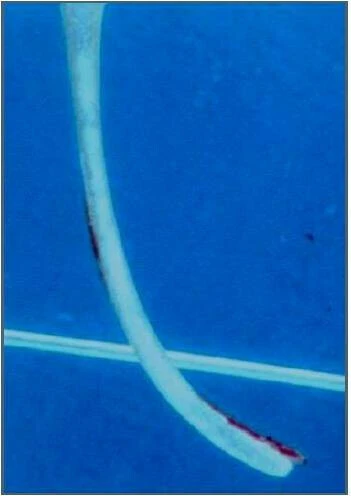

Trâm H với chuyển động cắt lên xuống trong thành ống tủy loại bỏ mô ngà nhiều ở thành ngoài đoạn cong (vùng cong lồi) có thể dẫn đến dịch chuyển ống tủy, thậm chí thủng chóp.

Điều này có thể được giải thích là do trí nhớ kim loại và thiếu khả năng duy trì độ cong ban đầu của dụng cụ. Đặc biệt, những trâm cỡ trên #20 với độ mềm dẻo kém sẽ có khuynh hướng thẳng lại trong những ống tủy cong. Một khi trâm đầu tiên bắt đầu cắt quá mức phần ngà dọc theo thành ngoài của đoạn cong thì khi lên những dụng cụ lớn hơn, điều này càng diễn ra mạnh hơn.

Trong hình bên dưới có thể thấy: trâm số nhỏ có thể uốn cong theo hình dạng ban đầu của ống tủy, sau khi nong rộng ống tủy với trâm số lớn hơn thì ống tủy có nguy cơ bị dịch chuyển.